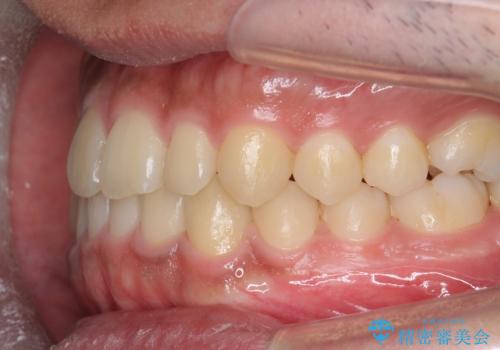

骨格性の受け口 非抜歯で下の歯を後ろに下げる インビザラインで インプラント矯正

治療により受け口が改善し、下あごの輪郭も若干後ろに下がった印象になりました。

当院では下の歯を後ろに下げるため矯正用ミニスクリューを用いてしっかり移動を行う等ご説明をし、治療開始しました。